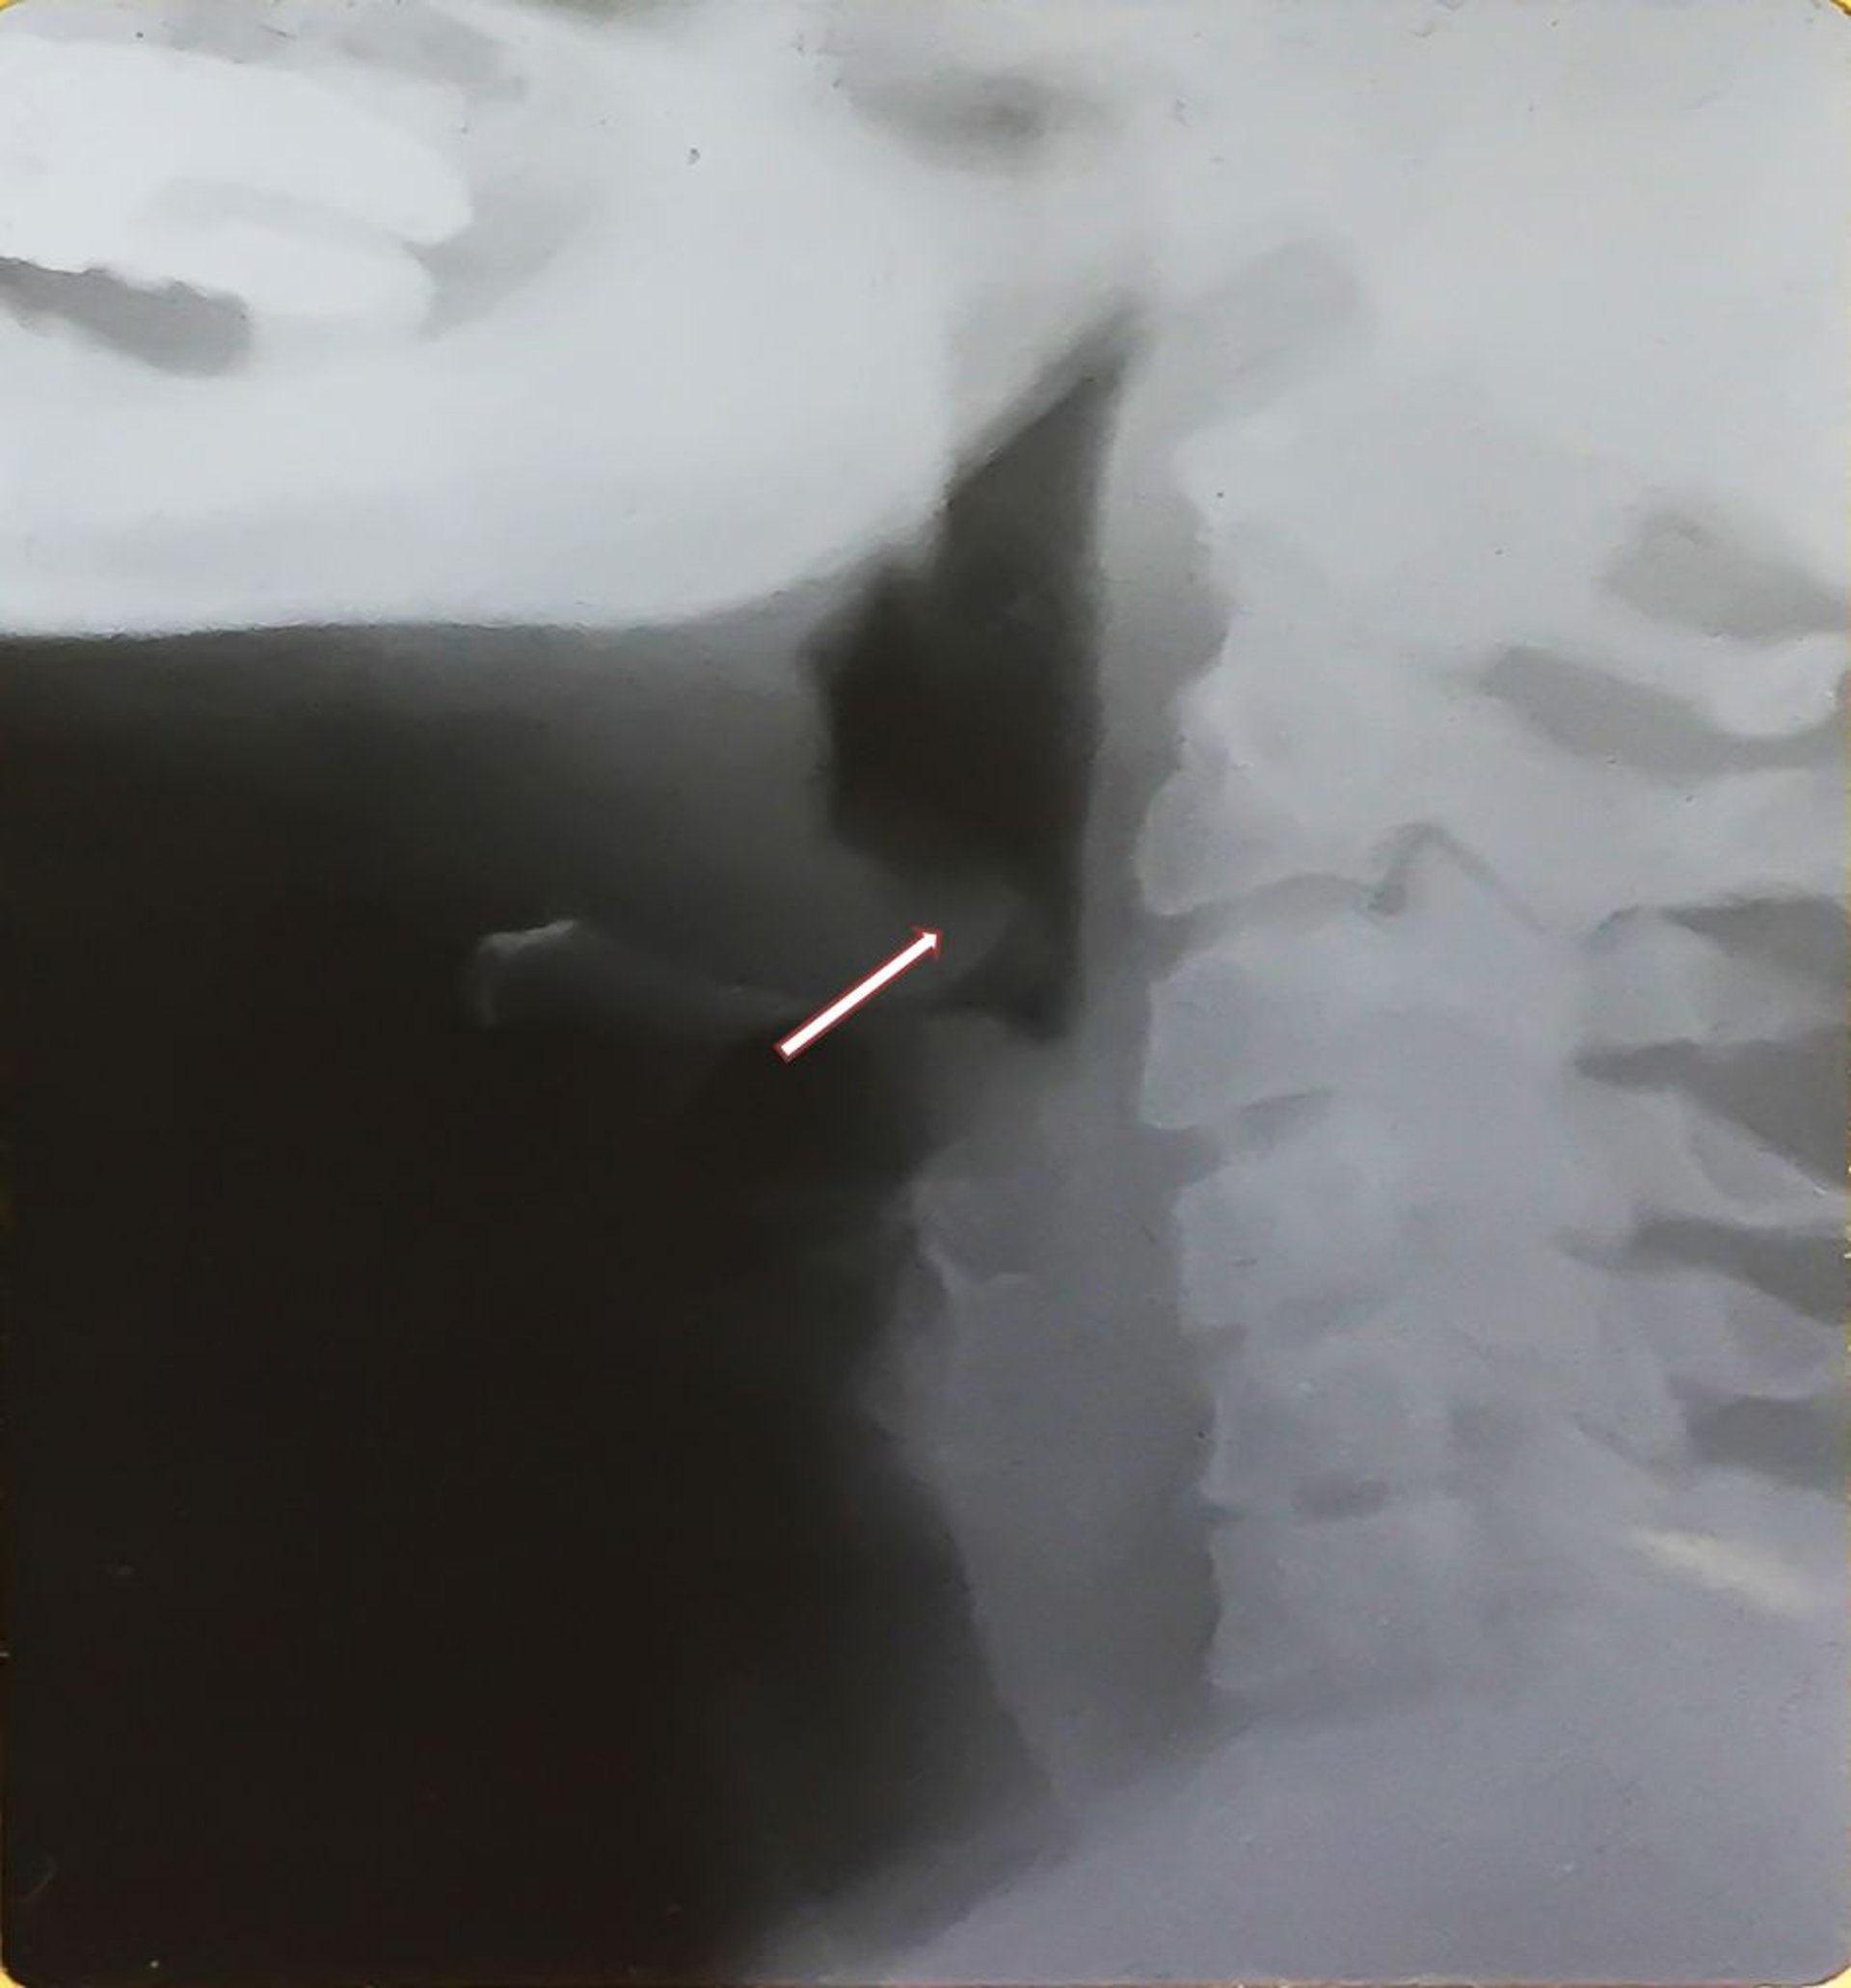

Épiglottite (adulte)

Cette radiographie montre l'épiglotte élargie (signe du pouce, voir flèche) caractéristique de l'épiglottite et de la distension de l'hypopharynx. Noter l'épiglotte épaissie, déplacée en arrière.

Image provided by Clarence T. Sasaki, MD.